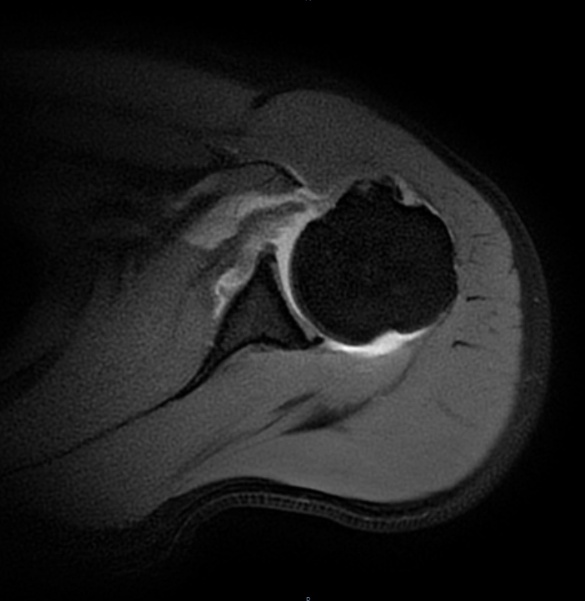

张华主任经过细致查体,怀疑这是肩胛下肌损伤。进一步的磁共振检查印证了判断,李先生肩胛下肌的止点位置撕裂了。“掰手腕时瞬间的力量不平衡,就像猛拉一根绷紧的绳子,很容易导致肩胛下肌急性撕裂。”张主任解释,李先生的这种损伤若不及时修补,肌肉会慢慢萎缩,不仅影响肩关节力量,还可能导致长期功能障碍。

为了帮李先生重新找回肩膀的“力量感”,张主任团队为他实施了关节镜下肩胛下肌撕裂修补术。手术采用微创方式,仅在肩部开几个不到1厘米的小孔,通过高清关节镜精准定位撕裂部位,再用带线锚钉,像缝衣服一样,将撕裂的肌腱牢牢缝合回原本的解剖位置。术后第二天,李先生的肩痛就明显减轻,终于能安心睡觉了。